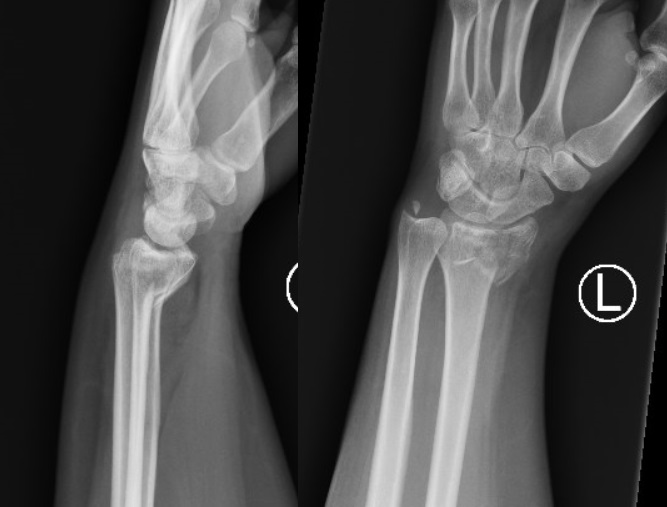

Diagnostikk

Røntgen (AP og sidebilde) bekrefter diagnosen og viser:

Brudd i distale radius med volar vinkling

Grad av dislokasjon, vinkling og eventuell leddaffeksjon

Tilstand i radiolunat og radioskaphoid-ledd